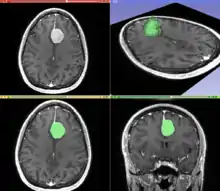

Information can take the form of images, sound, video or other multimedia. Bits of information can be streamed via signals. Its processing is the central notion of informatics, the European view on computing, which studies information processing algorithms independently of the type of information carrier – whether it is electrical, mechanical or biological. This field plays important role in information theory, telecommunications, information engineering and has applications in medical image computing and speech synthesis, among others. What is the lower bound on the complexity of fast Fourier transform algorithms? is one of unsolved problems in theoretical computer science.

![]() |

| FFT algorithms | Image processing | Speech recognition | Data compression | Medical image computing | Speech synthesis |